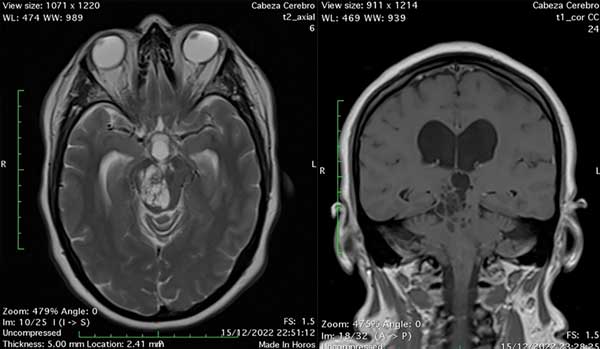

Una paciente de sexo femenino, de 51 años, con antecedentes de tabaquismo consultó por presentar un cuadro de incontinencia urinaria y fecal, trastornos de la marcha y deterioro cognitivo con un año de evolución. Se realizó tomografía computada (TC) de cerebro simple donde se evidenciaron múltiples imágenes hipodensas a nivel talámico bilateral y pontomesencefálico con dilatación del sistema ventricular supratentorial y signos de reabsorción transependimaria. Se efectuó una resonancia magnética (RM) de encéfalo que mostró múltiples imágenes quísticas localizadas en ambos tálamos, mesencéfalo y protuberancia, hipointensas en T1 y FLAIR, e hiperintensas en T2 sin realce tras la administración de contraste endovenoso compatibles con espacios de Virchow-Robin dilatados que causaban compresión del acueducto de Silvio provocando hidrocefalia obstructiva (Figura 2).

Figura 2. A la izquierda: imagen de RM de encéfalo en corte axial ponderada en T2 en la que se observan múltiples imágenes quísticas localizadas en mesencéfalo con dilatación ventricular asociada. A la derecha: imagen de RM de encéfalo en corte coronal ponderada en T1 en la que se observa la distribución mesencéfalo talámica de las lesiones quísticas. Nótese la isointensidad de las imágenes descriptas con el LCR y la ausencia de patrón de refuerzo tras la administración de contraste característico de espacios de Virchow-Robin dilatados.